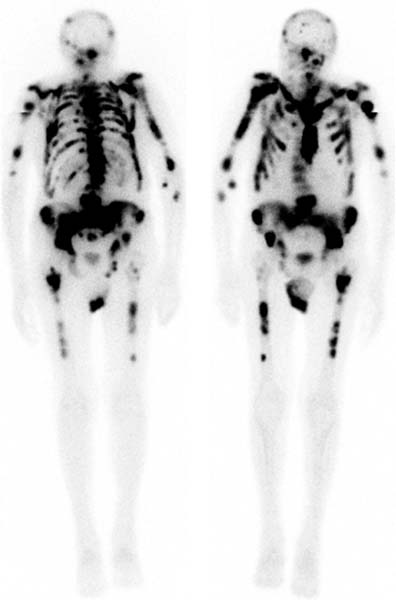

Bone Scans

Advantages of Bone scans over Conventional Imaging:

Early detection of bone metabolism changes, whole body screening

3 Phase Bone Scan: blood flow, blood pool, delayed.

Used for: osteomyelitis, prosthesis infection

Superscan

Intense skeletal uptake with reduced renal/ST activity (eg: metastatic disease)

Common Indications:

? bony mets

Infection

Trauma

Arthritis